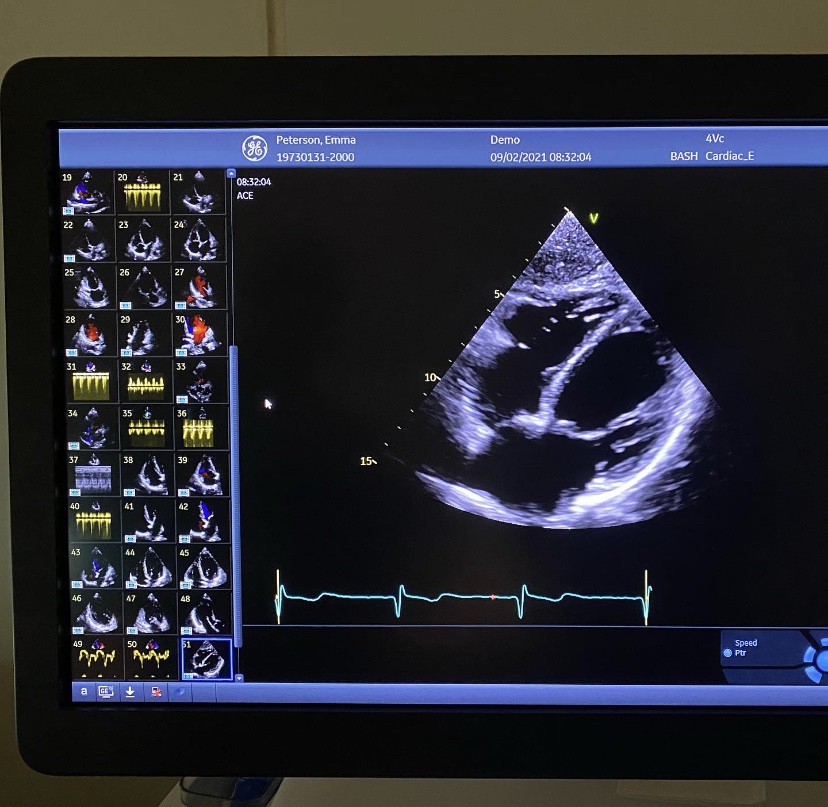

Först och främst: En stor eloge till sjukvården! Jag hann knappt lämna gårdagens läkarbesök, förens det ringde från den remiss läkaren just hade skickat iväg och en tid bokades till idag på morgonen. Det hann inte ens gå 18 timmar mellan de två olika besöken. Sjukvården får nog ta en hel del gnäll, personligen tror jag det ligger en liten del i det faktum att det är enkelt att gnälla om man själv inte riktigt vågar sig på en ordentlig undersökning. Sjukhus är ju inget som hamnar under kategorin Underhållande. (Med referens till den tesen, så skulle det med andra ord vara väldigt enkelt för mig att gnälla på… Tandvården)

Följetången fortsätter… ”Jakten på feber-orsaken”. Idag var jag på en hjärtundersökning. Undersökningen gick prima. Läkaren kunde inte se något direkt avvikande och jag slog nytt personbästa i att hålla andan. Ujjayi andning är👌🏼! Nu inväntar jag svaren som kommer om 7 dagar. Läkaren avrådde mig dock att under den närmaste veckan utföra någon form av hemma Yin yoga, insåg att där uppstår det ett problem… (Förlåt känsliga läsare) men jag anstränger mig mer och får en högre puls när jag (rebus) [🚽+💩] . Oj oj oj La La La.

Dagens chock, ja den fick väl min dotter när hon såg bilden… ÄR DU GRAVID???

Dottern mår efter omständigheterna också hon bra. Hm. Hur hög puls får man av Skratt?

Nu blir det att ta det lite piano. Mitt val med min läkare är här All in med ”uteslutningsmetoden”. Hittills 40 stycken blodprover och lungröntgen, vilka var superba